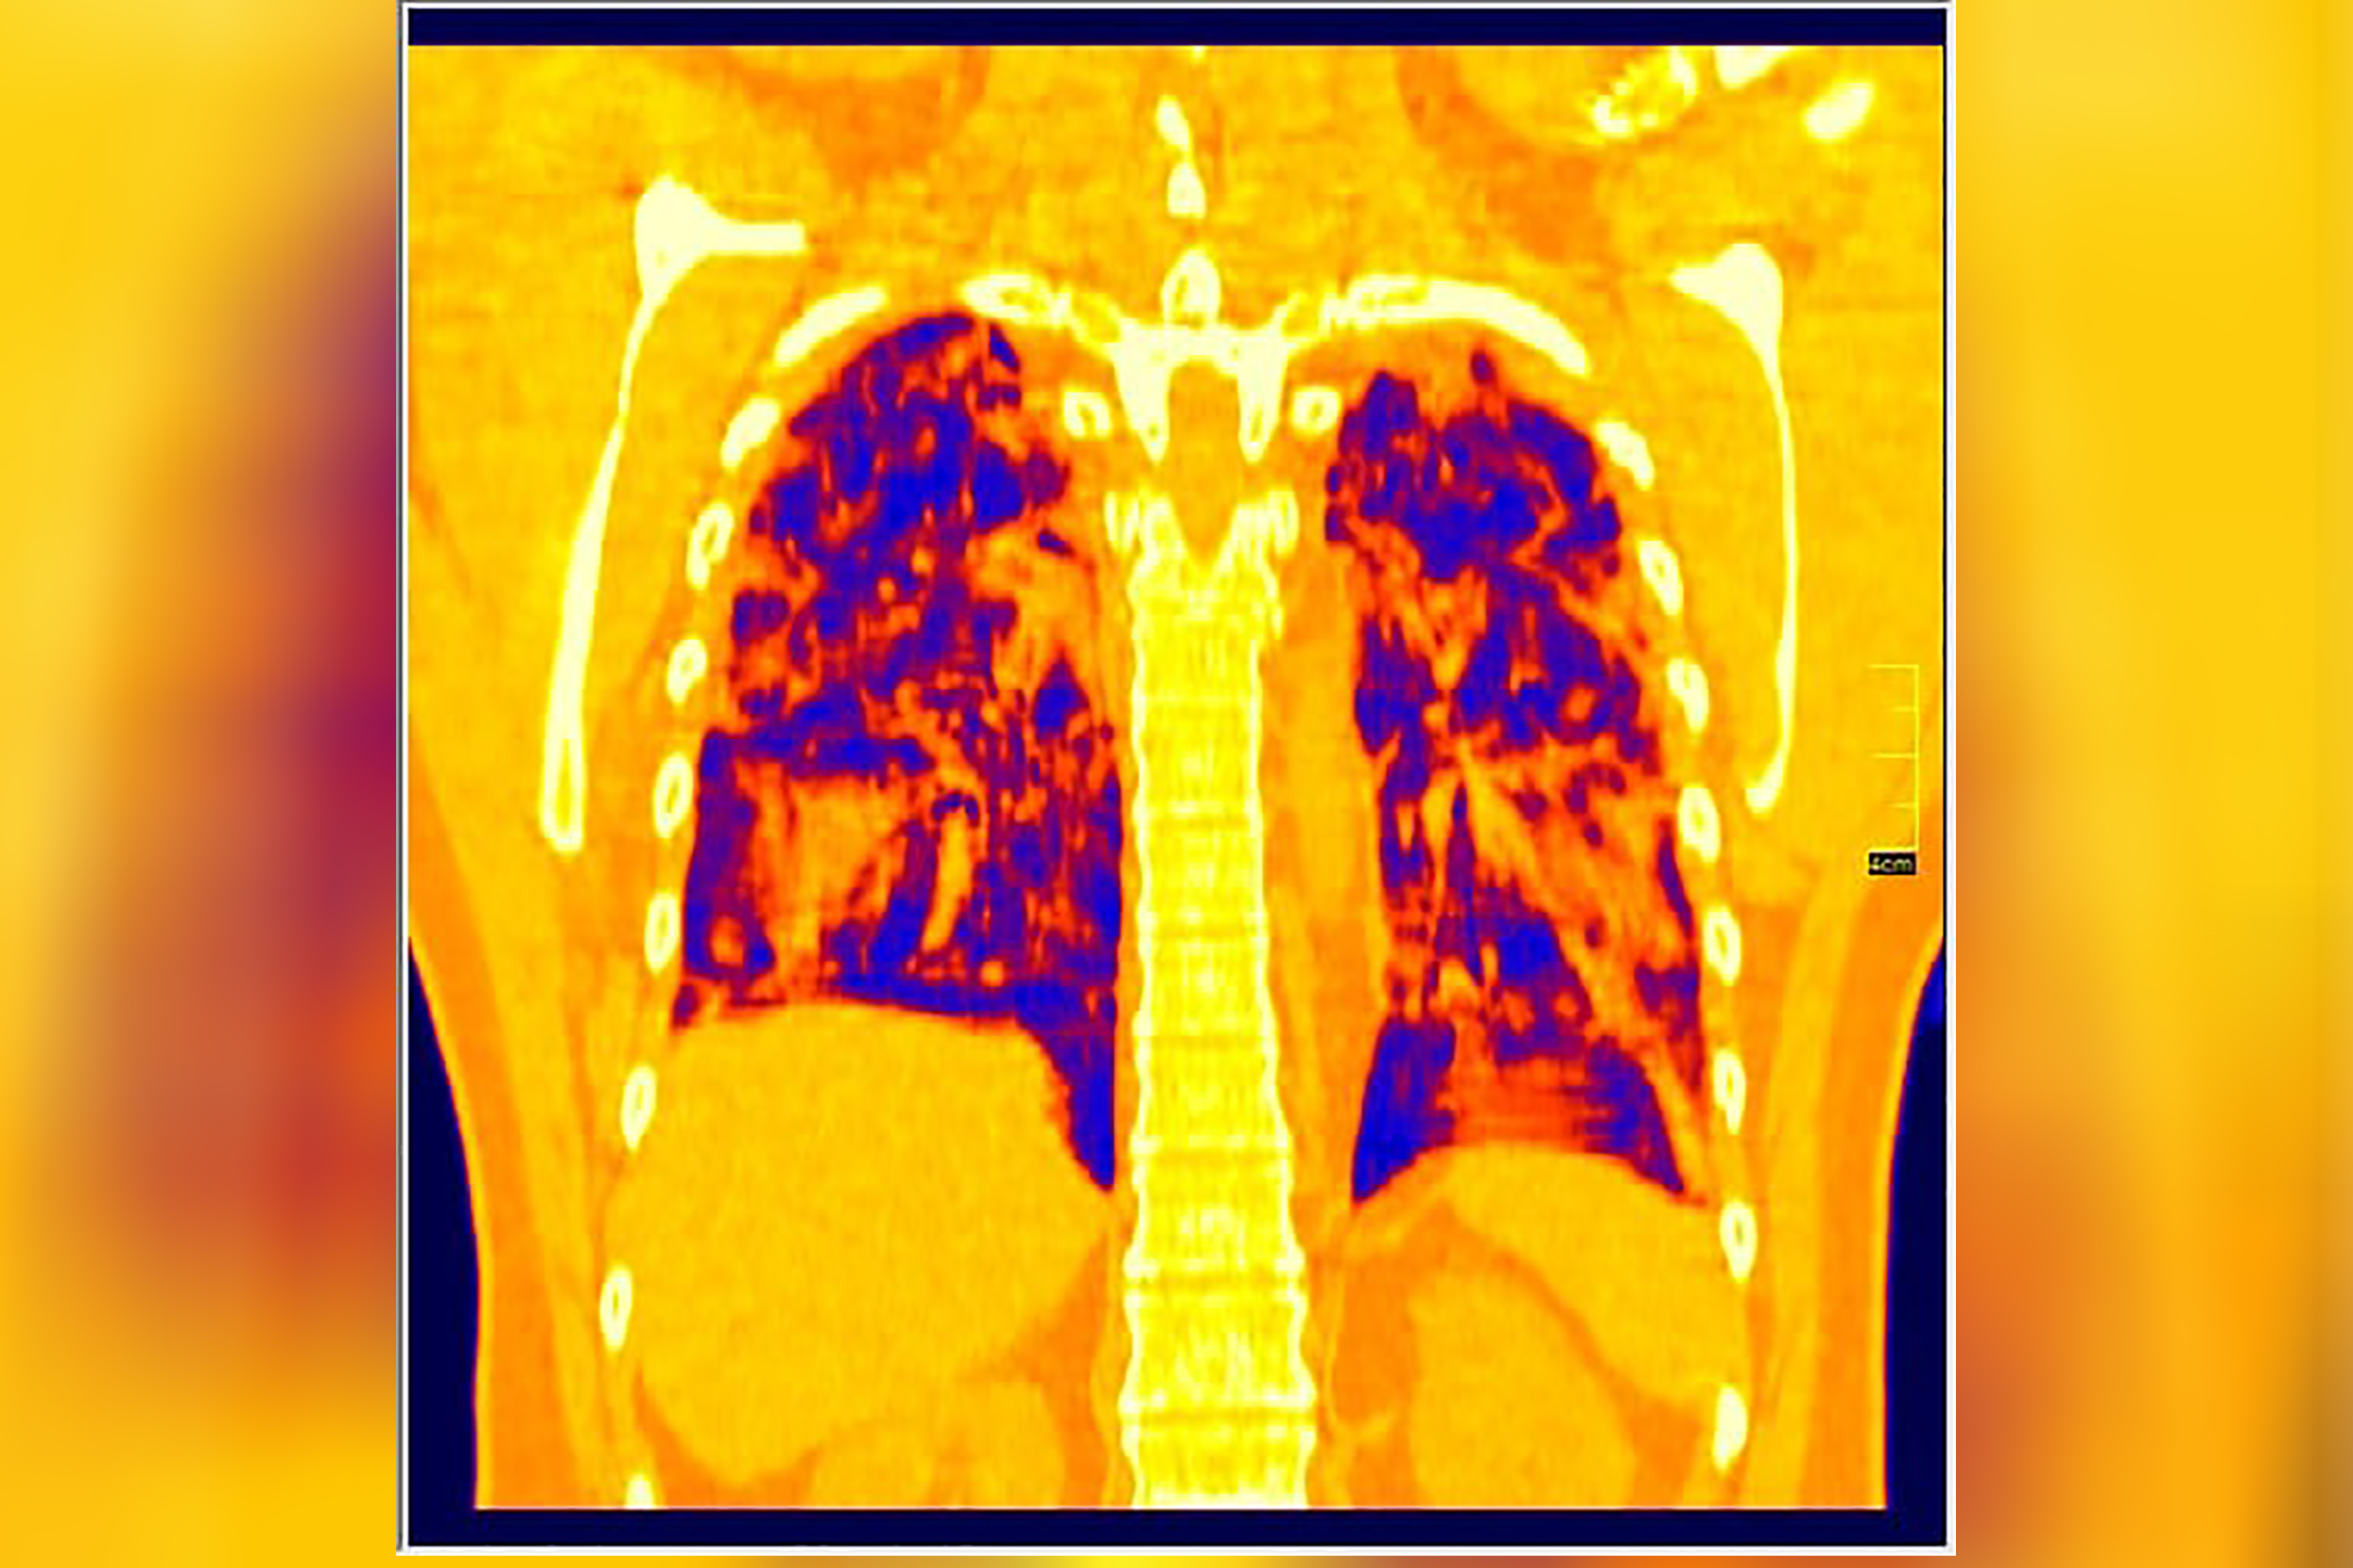

Foto: Aleksandar Ivković Foto: Aleksandar Ivković Foto: Aleksandar Ivković Zastrašujući snimci skenera pluća od 1. do 15. dana kovida autor: Božica Luković Zdravlje 26. nov. 2020. 12:33 > 26. nov. 2020. 13:35 0 Podeli vest: Kovid 19 je nepredvidiva bolest koja u razmaku od par dana može iz blage da preraste u opasnu po život. Kako koronvirus utiče na pluća iz dana u dan, pokazao je na snimcima CT skenera srpski radiolog Aleksandar Ivković. Podeli vest: Oglas Lekar iz Niša na svom blogu "Ljudi i ostale laži" redovno piše o svim važnim temama u vezi sa koronavirusom, a sada je odlučio da prikaže CT skenere pluća osobe obolele od kovida 19.Objasio je šta lekari tačno prate kada su u pitanju snimci pluća, ali i kako se te stavke menjaju kako bolest napreduje.Njegovu objavu prenosimo u celosti."Vraćam se na svoju usku struku (da ne bude da se mešam u tuđu). Kompjuterizovana tomografija, skener ili CT je metoda pregleda koja je superiorna kod zapaljenskih bolesti pluća. Kod kovida 19 se pokazala kao nezamenjiva u diferencijaciji u odnosu na ostale bolesti. Tačnost nalaza na plućima je visoka. Šta mi to možemo videti i kako tumačimo? Stvari koje pratimo su:- Ground glass konsolidacije (GGO).To su one bele "mrlje" na snimcima koje su karakteristične za ovu bolest. Nazivaju se "ground glass" svuda. Izgledaju kao da se taj deo pluća gleda kroz mlečno staklo, kao neka vrsta mikromozaika. Foto: Aleksandar Ivković | Foto: Aleksandar Ivković - Crazy paving.To su linearna zadebljanja koja se nekada vide u ground glass konsolidacijama. Ona nastaju kasnije, ne javljaju se pre GGO. Neko ih opisuje kao da pijani majstori slažu pločice. Na slikama se to vidi kao nepravilna zadebljanja unutar GGO, složena bez ikakvog reda. Foto: Aleksandar Ivković | Foto: Aleksandar Ivković - Vaskularne dilatacije. Dolazi do zapaljenskog procesa krvnih sudova i/ili do zastoja tako da su nam na snimcima krvni sudovi "deblji". Foto: Aleksandar Ivković | Foto: Aleksandar Ivković - Trakcione bronhiektazije. To su proširenja vazdušnog prostora (ali ne onog koji učestvuje u disanju) koja nastaju kada stradaju alveole i proširuje se prostor između njih. Foto: Aleksandar Ivković | Foto: Aleksandar Ivković - Arhitektonske distorzije. Pojava traka blizu pleure koje nastaju propadanja plućnog tkiva i nastanka fibroznog. Foto: Aleksandar Ivković | Foto: Aleksandar Ivković Svaki od ovih znaka se može javiti i kod drugih bolesti ali svi zajedno su specifični za kovid-19Da bi objasnili stanje koristimo Severity Score. On služi za procenu ozbiljnosti bolesti. Pluća se sastoje od pet lobusa. Procenjuje se svaki pojedinačno ocenama od 0 do 5. To znači da se skor kreće od 0 do 25.0 - znači da nema GGO konsolidacija1- znači da je manje od 5% tog lobusa zahvaćeno2 - znači da je zahvaćeno od 5 do 25% tog lobusa3 - znači da je zahvaćeno 26 do 50% tog lobusa4 - znači da je zahvaćeno 51 do 75% tog lobusa5 - znači da je zahvaćeno više od 75% tog lobusa Na CT razlikujemo 4 faze (najčešće ali nije decidirano tako) Rana faza (0 do 4. dan) - pojedinačne GGO, neka crazy paving, nizak skor Foto: Aleksandar Ivković | Foto: Aleksandar Ivković Progresivna faza (5. do 8. dan) - povećanje broja GGO i crazy paving Foto: Aleksandar Ivković | Foto: Aleksandar Ivković Pik faza (10. do 13. dan) - javljaju se konsolidacije pluća, to znači da veliki delovi pluća izgledaju kao velike bele površine a označavaju delove pluća koji su masa koja koja je u celini zahvaćena zapaljenskim procesom. Foto: Aleksandar Ivković | Foto: Aleksandar Ivković Faza rezolucije (posle 14. dana) - vraćanje delova pluća u normalu ili smrt Foto: Aleksandar Ivković | Foto: Aleksandar Ivković Iskustveno smo došli do skora 15 koji predstavlja neku granicu između verovatno dobrog i verovatno lošeg ishoda. Samo tumačenje zavisi od faze bolesti. Naš nalaz je samo deo procene i ne menja laboratorijske i pulmološke, kao ni ostale. Svaki nalaz zajedno daje ukupnu sliku bolesti. Foto: Aleksandar Ivković | Foto: Aleksandar Ivković Nalaz je u88% slučajeva sa obe strane,88% ground glass,80% posteriorno,79% multilobularno,76% periferno i30% konsolidacijeTo je posao radiologa, to je moj posao. Sasvim sigurno je da bez ovih slika lečenje ne bi bilo lako. Pacijente delimo na lake - one koji nemaju tegobe, teške - one koji imaju zahvaćeno do 50% pluća i kritične a to su oni kod kojih je više od 50% zahvaćeno", piše dr Ivković.***Bonus video:https://www.youtube.com/watch?v=fYeYlhqeD5cPratite nas i na društvenim mrežama:FacebookTwitterInstagram Revolucija iz Niša: Test na koronu koji predviđa tok bolesti Zdravlje 0 Tekst naučnika koji ruši sve zavere o koroni - i daje nadu Zdravlje 0 72 sata pakla od kad su me zabolela pluća u kovid Srbiji Zdravlje 0 aleksandar ivković ct skener koronavirus kovid-19 pluća Pratite nas na društvenim mrežama: Koje je tvoje mišljenje o ovoj temi? Učestvuj u diskusiji ili pročitaj komentare Budite prvi koji će ostaviti komentar Pošalji komentar Pročitaj komentare (0)